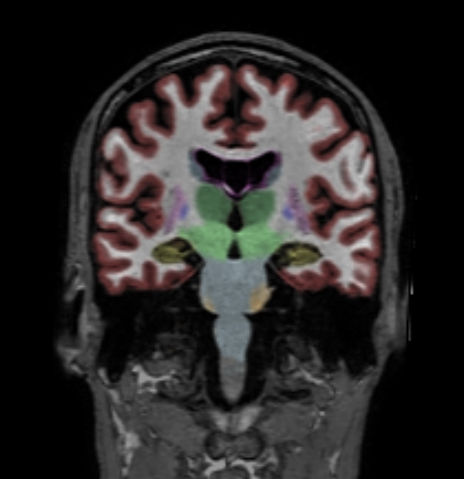

Coronal reformat 3D T1w TFE with NeuroQuant segmentation